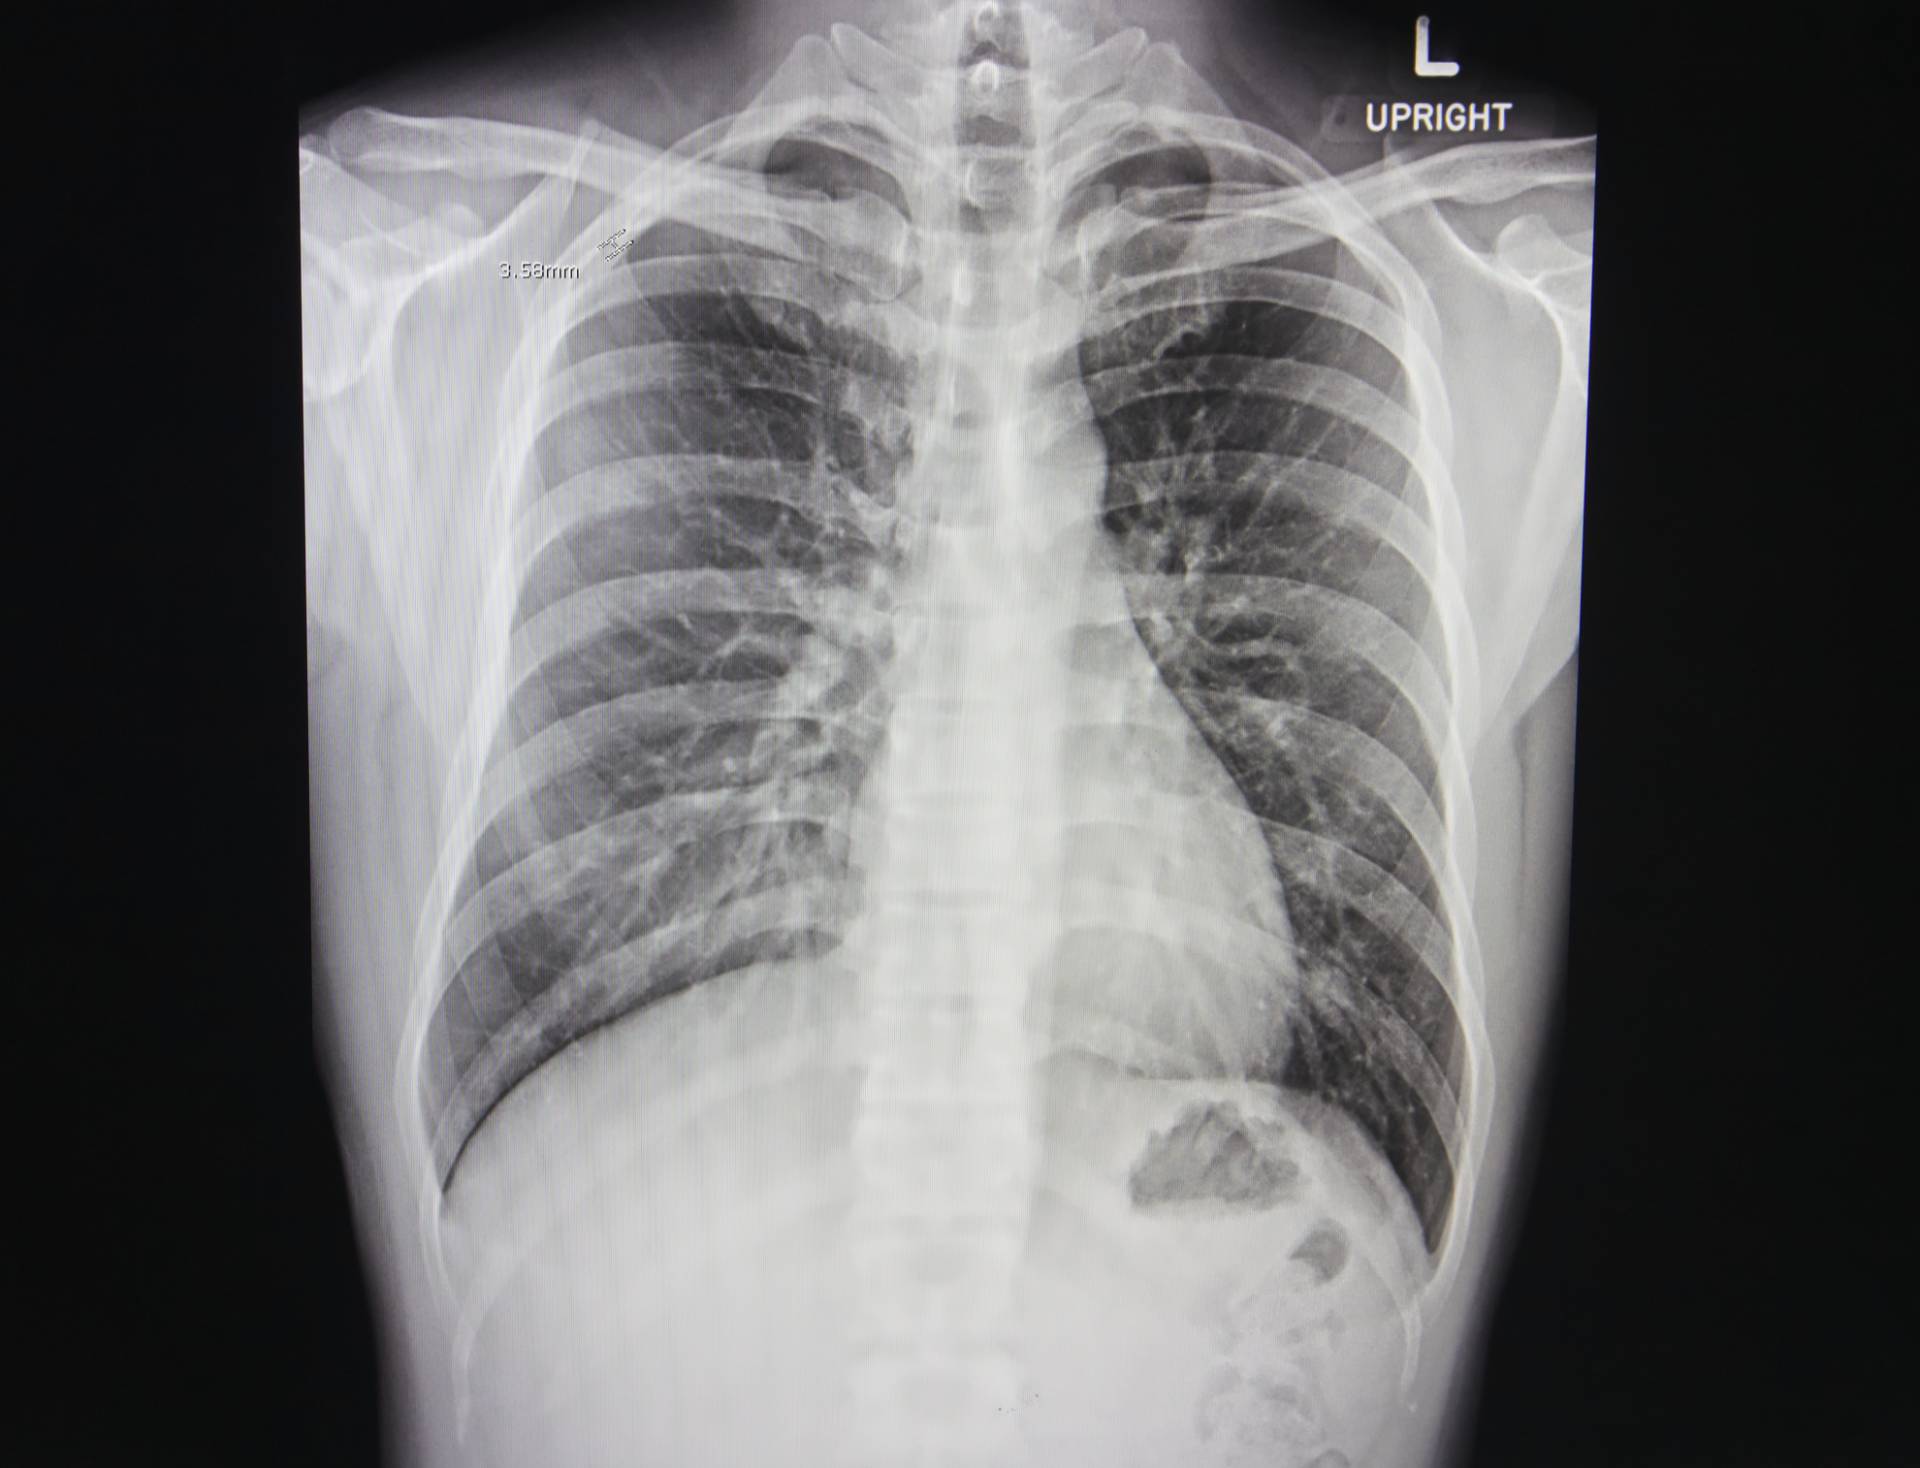

qXR, deep learning AI software swiftly analyses Chest X-rays to triage scans for patients with lung cancer suspicion, enhancing efficiency and shortening time to diagnosis

Lung cancer is the biggest cause of cancer deaths in the UK. 5-year survival rate is poor at just 14.6% and 30% of patients die within 90 days of diagnosis, with around 48,600 new cases and 35,300 deaths annually. The National Optimal Lung cancer Pathway (NOLCP) recommends rapid progression from chest X-ray (CXR) to computerised tomography (CT) scan to reduce time to diagnosis for Lung cancer patients. However, radiology capacity and increasing workload hinders implementation of NOLCP, with the current average time at 63 days. Recently published work found that immediate radiographer CXR reporting and triage straight to CT significantly reduced time to diagnosis of Lung cancer by almost half from a median of 32 days compared to routine CXR reporting. Using qXR, an Artificial Intelligence (AI) solution for immediate CXR reporting should have a similar impact on time to diagnosis.

qXR is AI-powered X-ray software which will be utilised for triaging CXRs immediately after they have been captured. This triage should allow for quicker and more accurate reporting. The project investigates the impact of AI triage of CXRs against routine non-triaged reporting on time to CT and final diagnosis of a patient. The triage alert could lead to faster reporting of suspicious X-rays reducing the wait time for CT appointments. qXR double-read also enhances accuracy of reporting, potentially improving lung cancer detection. The project tests AI CXR triage using qXR across NHS sites, assessing clinical effectiveness, economic viability, and integration. Data collection measures impact on Lung cancer diagnosis time, influencing NOLCP implementation.

In a recent study conducted with a high sensitivity operating point, qXR had a specificity of 83% on normal versus abnormal triage. The false positive rate would be around 17% (Diagnostics 2022, 12(11), 2724).